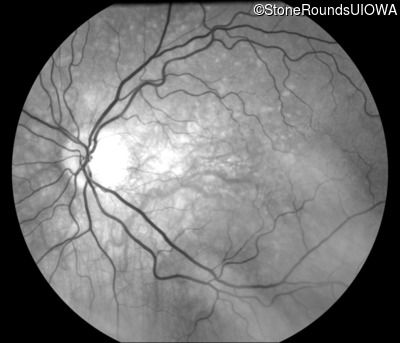

Infrared Fundus Photograph - Right - 20/20 -3 sc

Exemplar

Infrared Fundus Photograph - Left - 20/30 -2 sc